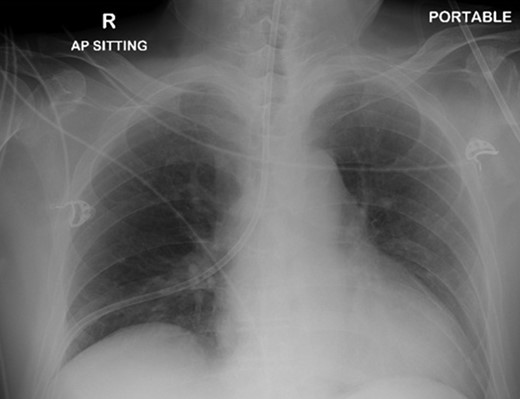

The patient was urgently reviewed by the cardiothoracic surgeons, and a small-bore chest tube was inserted, following which a computed tomography of the thorax was performed. This showed a residual but smaller pneumothorax with the chest tube in situ, associated with a small hemothorax (Fig. 3). Due to failure of conservative management and concern of a bronchopleural fistula resulting in air leak, he underwent explorative thoracoscopic surgery. Intraoperatively, an area of lung was noted with contusional changes and a bleb (Fig. 4), and a wedge resection of the right lower lobe was performed (Fig. 5). He made an uneventful recovery and was discharged.

Representative axial slice of computed tomography thorax showing a residual but smaller pneumothorax with the chest tube in situ.